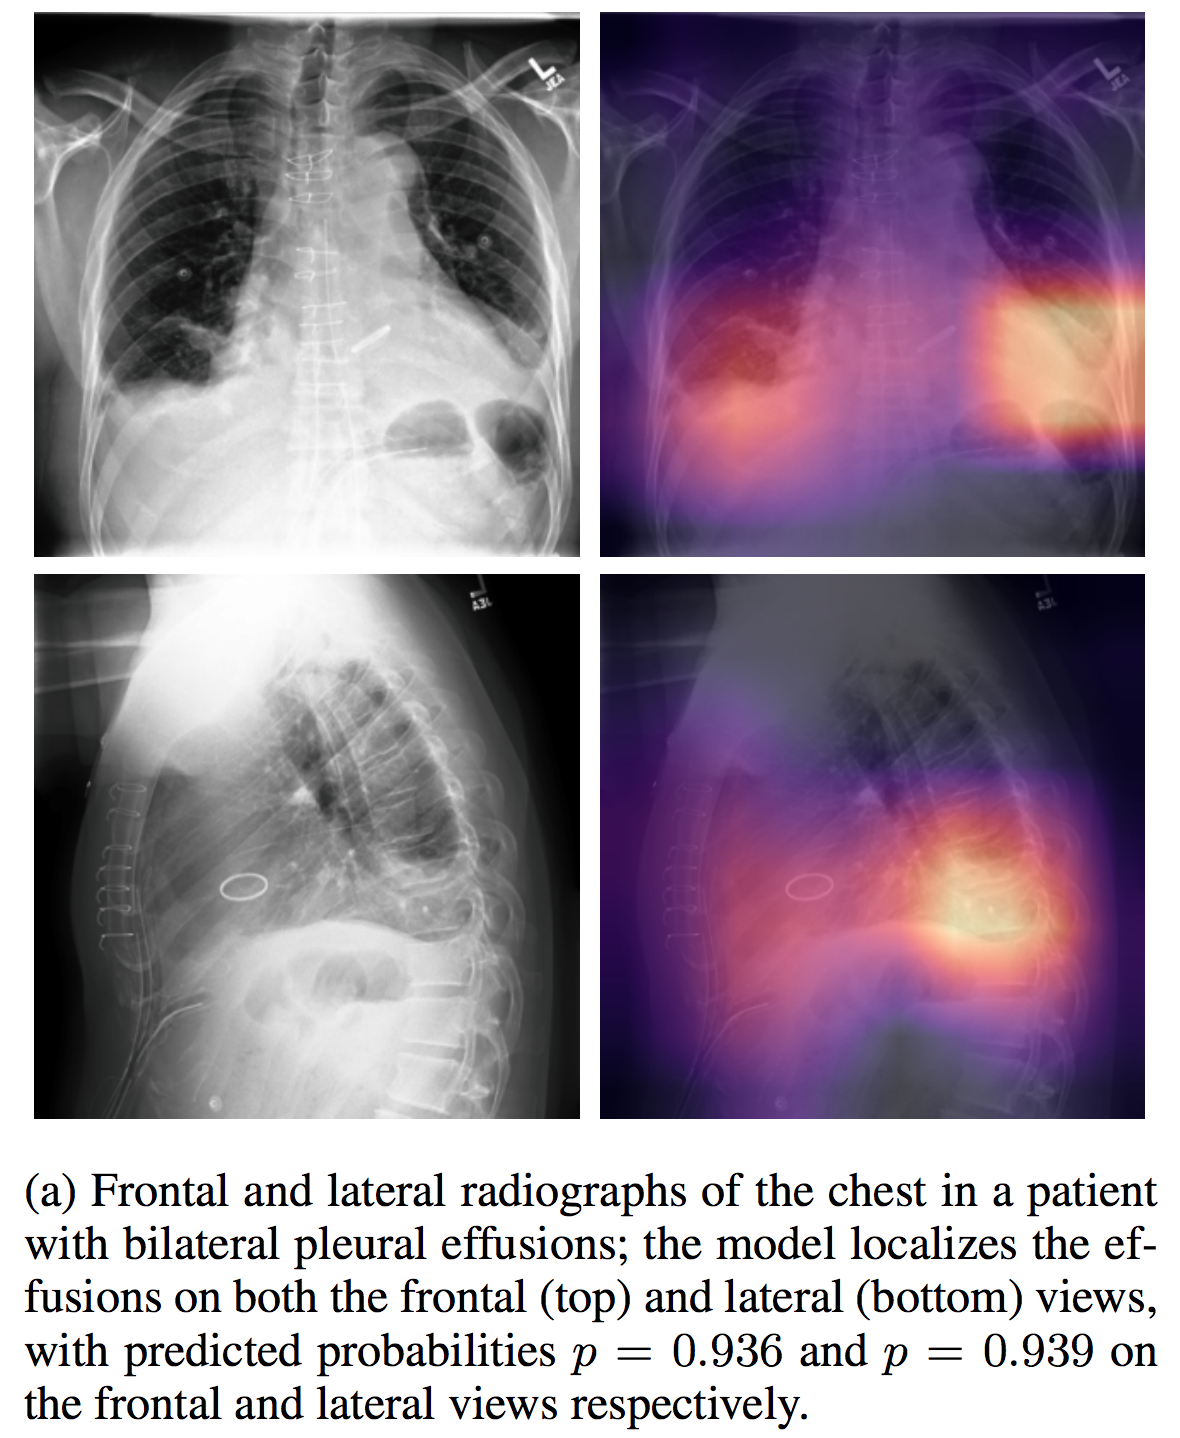

## CheXpert

| [CheXpert](https://stanfordmlgroup.github.io/competitions/chexpert/) | | | | | | |

介绍论文: [CheXpert: A Large Chest Radiograph Dataset with Uncertainty Labels and Expert Comparison](https://arxiv.org/abs/1901.07031)

## NIHChest Xray

| [NIHChest Xray](https://www.kaggle.com/nih-chest-xrays/data) | | | | | | CC0: Public Domain | | |

介绍论文: [ChestX-ray8: Hospital-scale Chest X-ray Database and Benchmarks on Weakly-Supervised Classification and Localization of Common Thorax Diseases](http://openaccess.thecvf.com/content_cvpr_2017/papers/Wang_ChestX-ray8_Hospital-Scale_Chest_CVPR_2017_paper.pdf)